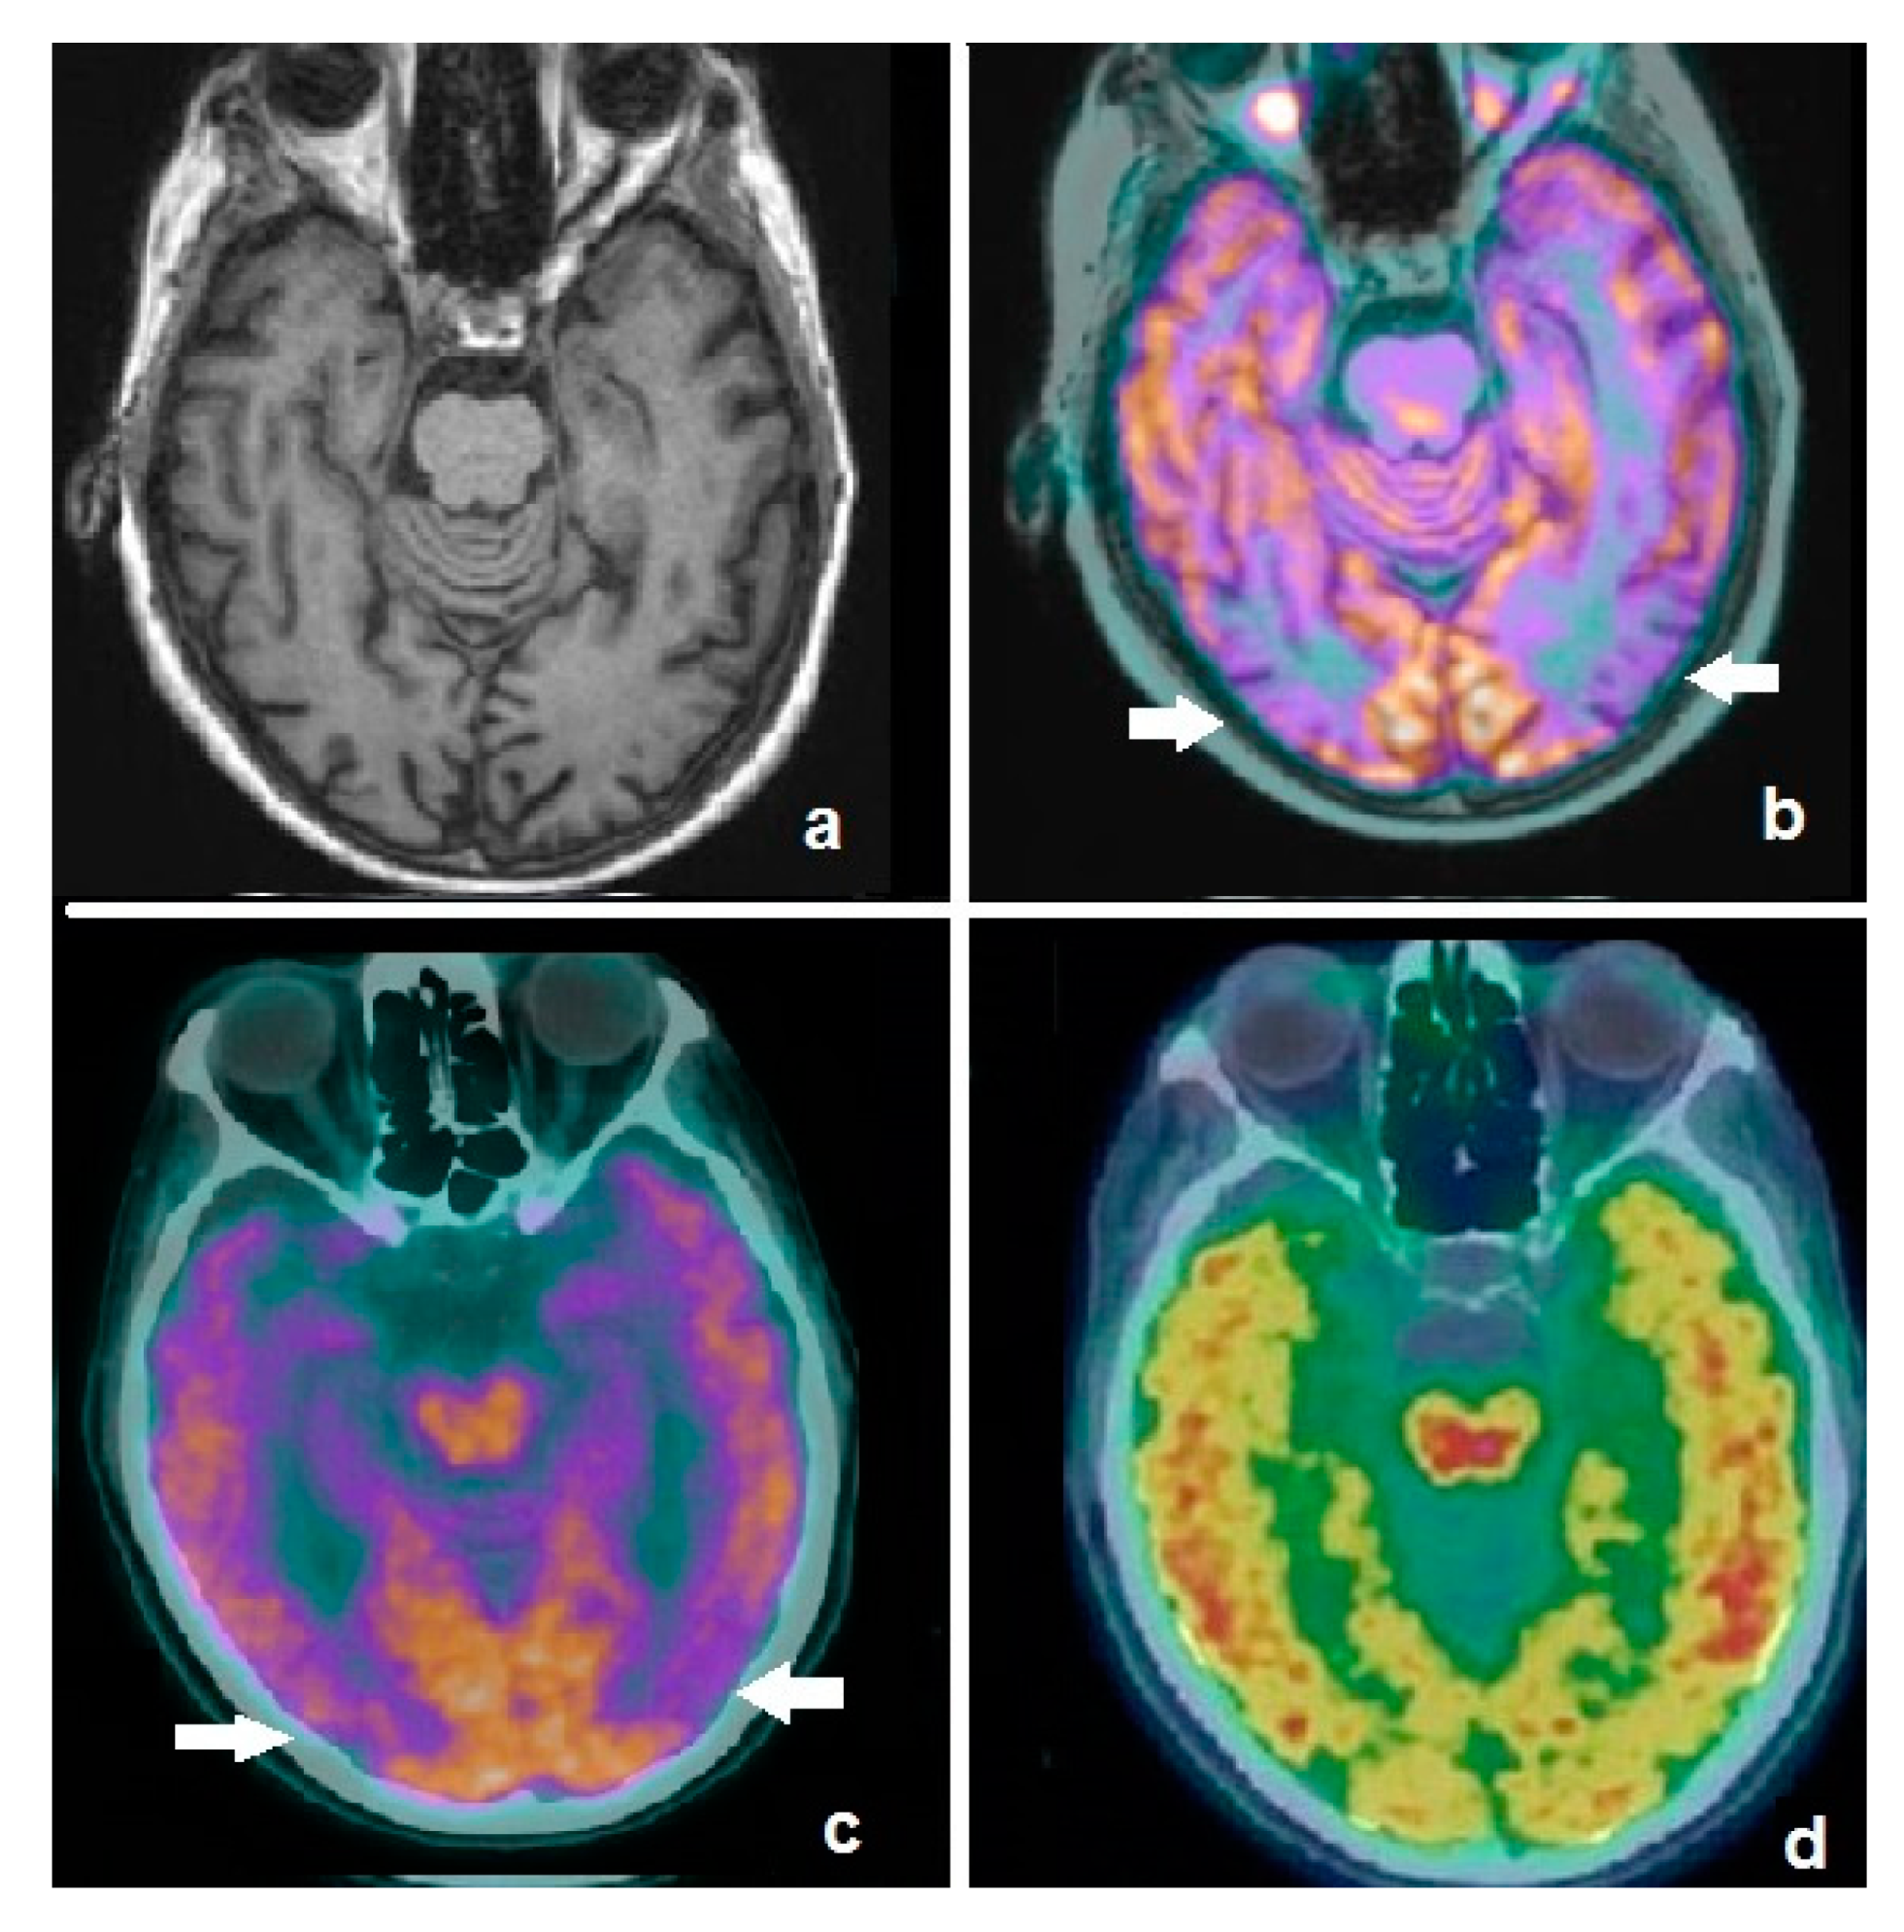

4.3. FDG-PET Imaging in SNCApathies

- Tang, C.C.; Poston, K.L.; Eckert, T.; Feigin, A.; Frucht, S.; Gudesblatt, M.; Dhawan, V.; Lesser, M.; Vonsattel, J.P.; Fahn, S.; et al. Differential diagnosis of Parkinsonism: A metabolic imaging study using pattern analysis. Lancet Neurol. 2010, 9, 149–158. [Google Scholar] [CrossRef]